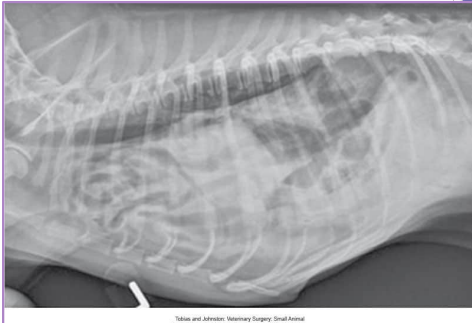

Diaphragmatic Hernia

Et: trauma, pressure gradient disruption, genetic

abdominal organs migrate into thorax, liver is #1

Peritoneopericardial d. hernia (PPDH) → congenital

Sig: Cocker spaniel, Weimaraner, Himalayan, DLH

Cs: shock(acute), dyspnea(chronic), exercise intolerance, ADR

Congenital is asymptomatic

Tears → weakest areas: muscle

Dt: thoracic rads (#1), US, CT

Tx: Sx (8-16w if congenital) (trauma: be ready for anything)

abdominal explore, identify hernia, reduce contents, close defect (absorbable 3-0 PDS, simple continuous, dorsal → ventral), remove air

Caution of adhesions

Do not close the pericardial sac (genetic)

Risk: re-expansion pulmonary edema, abdominal compartment syndrome, ARDS

Do NOT manually re-expand lungs, do not close pericardial sac